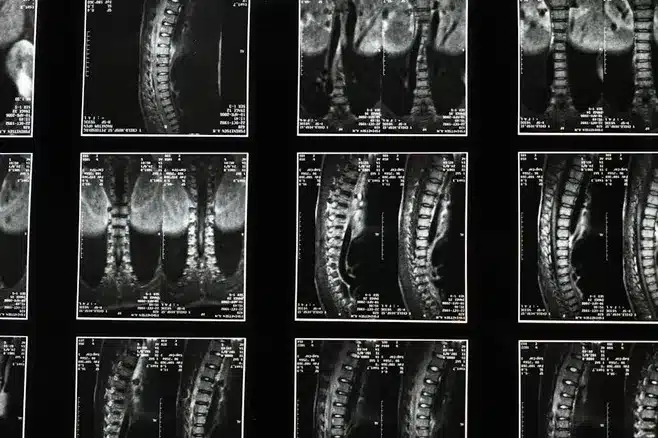

Los nervios espinales son fundamentales para la comunicación entre el sistema nervioso central y el resto del cuerpo. Estos nervios se extienden desde la médula espinal y se dividen en 31 pares que se encargan de transmitir información sensitiva y motora a diferentes partes del cuerpo. Cada par de nervios tiene una función específica y es importante conocerlas para entender mejor cómo funciona nuestro cuerpo y cómo podemos mantenerlo en buen estado.

Los nervios espinales son una parte del sistema nervioso periférico que se encarga de transmitir información entre el sistema nervioso central y las diferentes partes del cuerpo. Se dividen en 31 pares y están compuestos por fibras nerviosas que se encargan de transmitir información sensitiva y motora.

Nervios espinales lumbares (L1-L5)

– L1-L3: inervan los músculos de la cadera y de la pierna.

– L4-L5: inervan los músculos de la pierna y del pie.

Nervios espinales sacros (S1-S5)

– S1-S2: inervan los músculos de la pierna y del pie.

– S3-S5: inervan los músculos del ano y de los genitales.